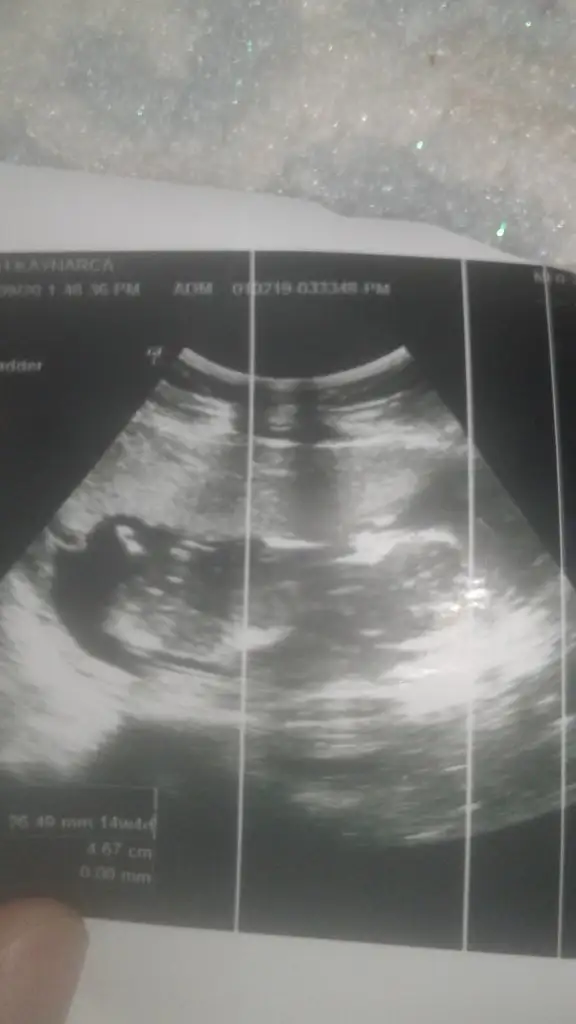

Ikra meyra Ikra meyra 14 hafta 4 günlük. Rica etsem tahminde bulunur musun

1600257590681359598552.webp